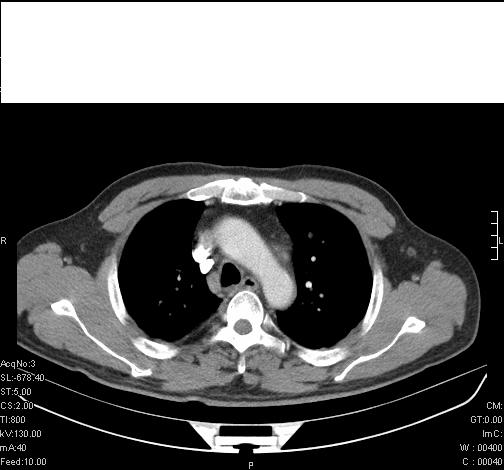

标题: CT6685:右肺阻塞性炎症,增强CT。

前几天,发了患者的平扫片,患者抗炎一周后增强扫描。右中叶病灶吸收明显,但下叶病灶未见明显吸收。右肺门可见结节影,看来凶多吉少

右肺下叶支气管管腔狭窄,管壁增厚,右下肺见斑片状高密度影,考虑右侧肺门中心肺癌伴阻塞性肺炎

右肺下叶支气管壁明显增厚,考虑癌症并阻塞性炎症、肺门淋巴结肿大

考虑右肺癌并阻塞性炎症、肺门淋巴结肿大

右肺下叶支气管壁不规则增厚,右肺下叶有斑片状影分布。考虑右肺中央型肺癌伴右肺下叶阻塞性改变。建议支纤镜检查。平扫比增强较好显示了病变情况。

右主支气管狭窄,管壁增厚。考虑右中心性肺ca伴阻塞性肺炎。

既然抗炎治疗有效,可继续治疗;右肺下叶支气管管腔狭窄,管壁增厚,右下肺见斑片状高密度影,右侧主支气管后见结节影(淋巴结?),肺癌不能排出。